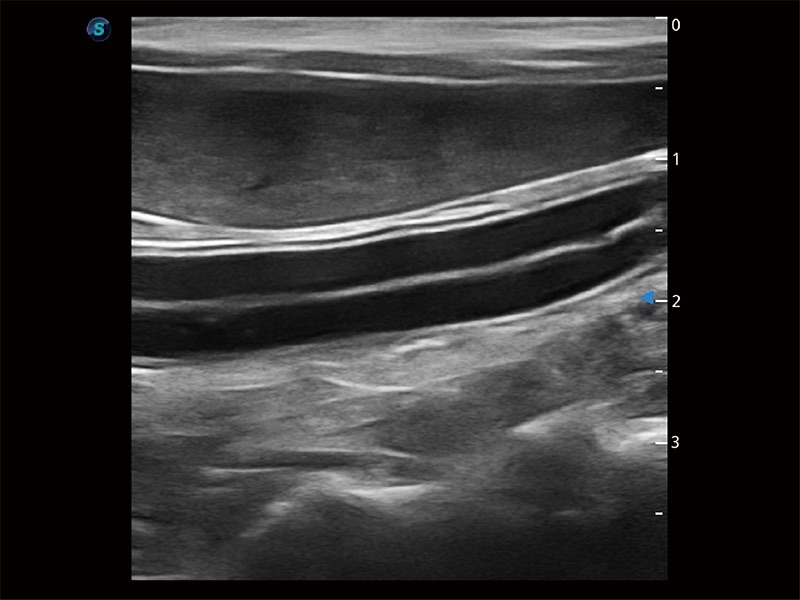

高性能和先进的临床应用工具可以为动物医生提供临床信心。ProPet 80 搭载了先进的腹部和浅表应用工具,帮助医生在日常临床实践中发挥前所未有的作用。

操作简便,无需高频度外力作用即可真实反映组织的形变,快速评估肿瘤良恶性。